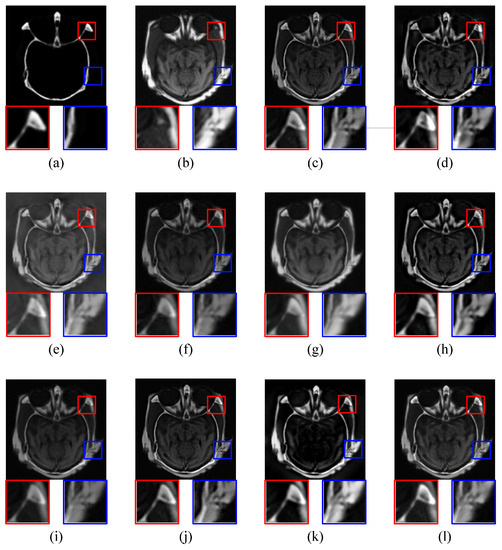

4.2.1. CT-MRI Image Fusion Comparative Experiments